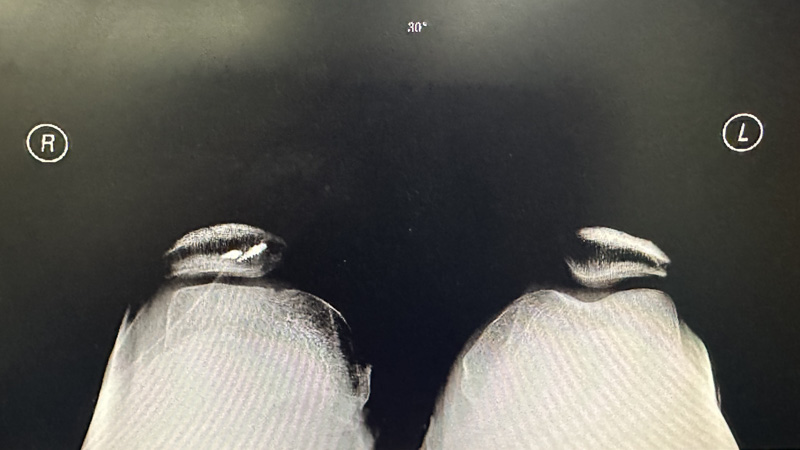

▲跟健側對比:膝關節屈膝30°,髕骨脫位

經仔細檢查后,柳州市人民醫院運動醫學科副主任韋釗嵐發現王先生的膝關節屈曲30°時,髕骨就脫位跑到了股骨滑車外側,整個屈膝過程髕骨都不能復位,直到再次伸直膝關節,髕骨才能回位,這是很明顯的“屈曲型習慣性髕骨脫位”。